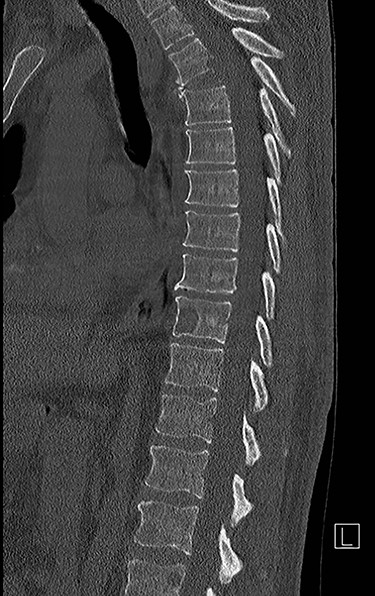

Spinal images are presented in Figs 1–6. Cross-sectional imaging revealed no other neoplastic lesion. He received dexamethasone 10 mg bolus then 4mg four times daily with appropriate proton pump inhibitor coverage. Due to no distinguishable major arterial feeder upon review of the imaging jointly with the neuroradiologist, pre-operative embolization was not attempted. The following morning, he underwent posterolateral right costotransversectomy, ligation of the ipsilateral T4 nerve root, T4 vertebrectomy and insertion of an expandable titanium cage with T1–T7 pedicle screw fixation (Figs 7 and 8). Post-operatively his pain improved to VAS 2/10 and motor power in his left lower limb improved to MRC grade 4/5. The patient was discharged home Day 10 post-admission with physiotherapy.

Sagittal computed tomography (CT) scan demonstrated multiple lytic lesions and pathological fracture of the T4 vertebra with almost complete collapse along with kyphotic deformity.

The patient presented with thoracic kyphosis and clinical evidence of mechanical pain. The radiological images showed evidence of three-column involvement of the T4 lytic lesion. Adjacent bilateral pedicle fracture of T5 offered no additional structural support and therefore this degree of deformity was not surprising. This spinal instability neoplastic score (SINS) [3] of 14/18 and grade 3 epidural spinal cord compression (ESCC) [2] were in support of surgical decompression and stabilization [2, 3]. A number of approaches were considered including anterior transcavitary, posterolateral extrapleural approaches and posterior decompression and instrumentation, with or without insertion of expandable titanium cage [1]. Laminectomy alone or with radiotherapy was not an option in this case as it would have offered very little decompression of this anteriorly compressing lesion as well as exacerbate the deformity by further sacrificing the posterior elements, thereby offering no contribution at structural stability.